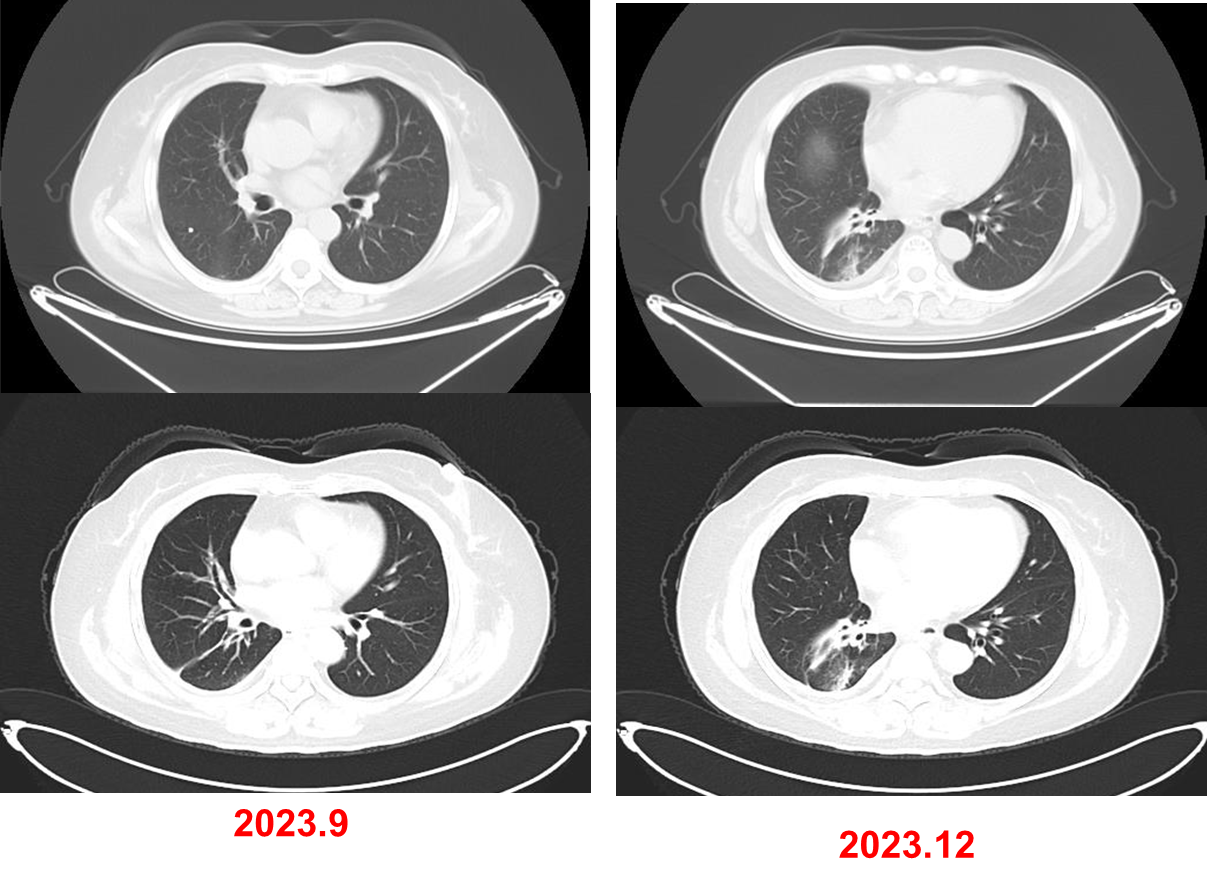

2024年7月至2025年4月,行长春瑞滨软胶囊(40mg,每周一、三、五)口服治疗。

疗效评估:PR。

基于上述证据并尊重患者意愿,本例患者三线采用口服长春瑞滨节拍化疗,疗效评估达到PR。截至末次随访时间(2025年4月),患者连续用药9个月余,无明显不良反应,疾病控制稳定,初步实现晚期肺癌的长期慢病化管理。